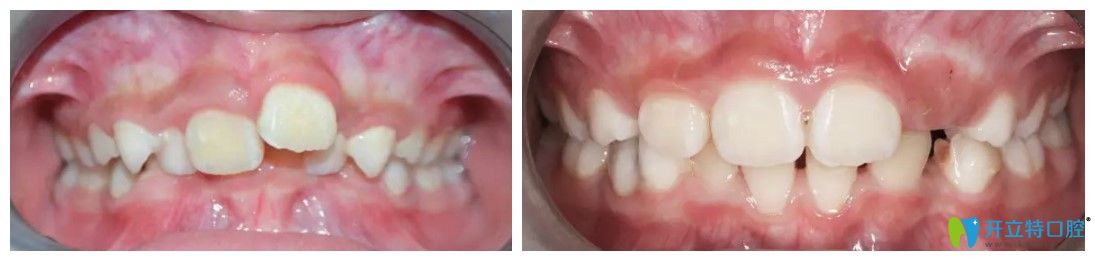

患者:西西

年齡:7歲

主治醫(yī)生:王聰

牙齒情況:替牙期牙列擁擠、前牙深覆合

超龍牙博士口腔兒童深覆合矯正案例圖